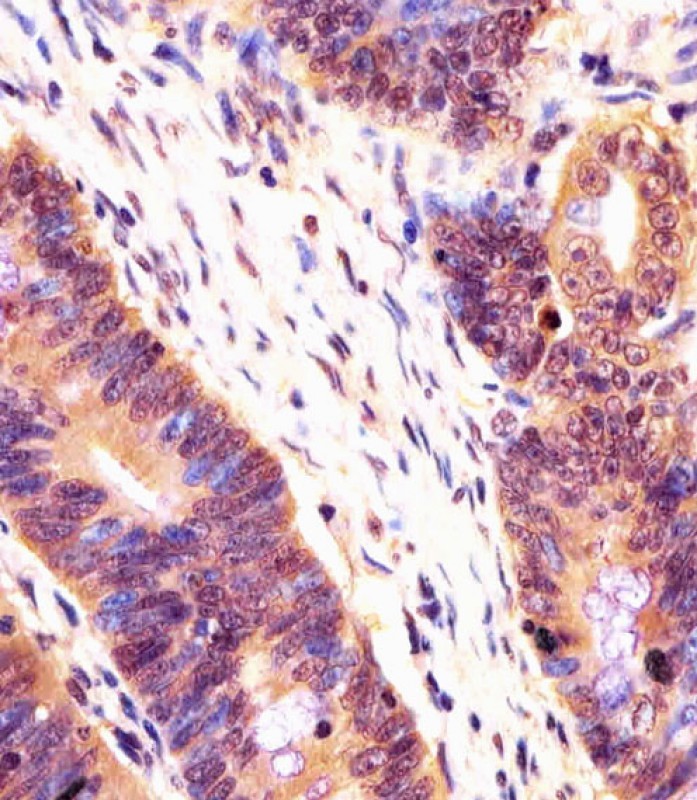

APR06959G staining PSMB7 in human colorectal carcinoma tissue sections by Immunohistochemistry (IHC-P - paraformaldehyde-fixed, paraffin-embedded sections). Tissue was fixed with formaldehyde and blocked with 3% BSA for 0. 5 hour at room temperature; antigen retrieval was by heat mediation with a citrate buffer (pH6). Samples were incubated with primary antibody (1/25) for 1 hours at 37°C. A undiluted biotinylated goat polyvalent antibody was used as the secondary antibody.